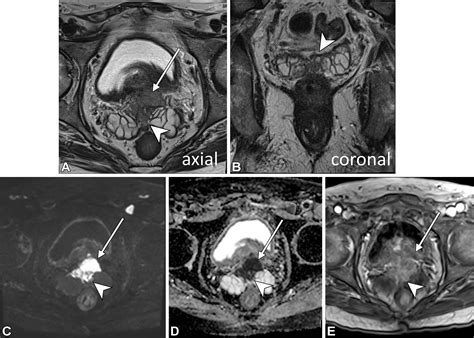

• Multiparametric MRI (mpMRI): This advanced technique combines several MRI sequences to provide a comprehensive evaluation of the prostate. It includes:

• T2-weighted imaging: Provides detailed anatomical images of the prostate.

• Diffusion-weighted imaging (DWI): Measures the movement of water molecules within tissues to detect areas of restricted diffusion, which may indicate cancer.

• Dynamic contrast-enhanced (DCE) MRI: Uses a contrast agent to assess blood flow and vascularity within the prostate, helping to identify areas of increased blood flow that may be associated with cancer.

• Accurate staging: MRI can help to accurately stage prostate cancer by assessing the extent of the tumor and whether it has spread to nearby tissues or lymph nodes.